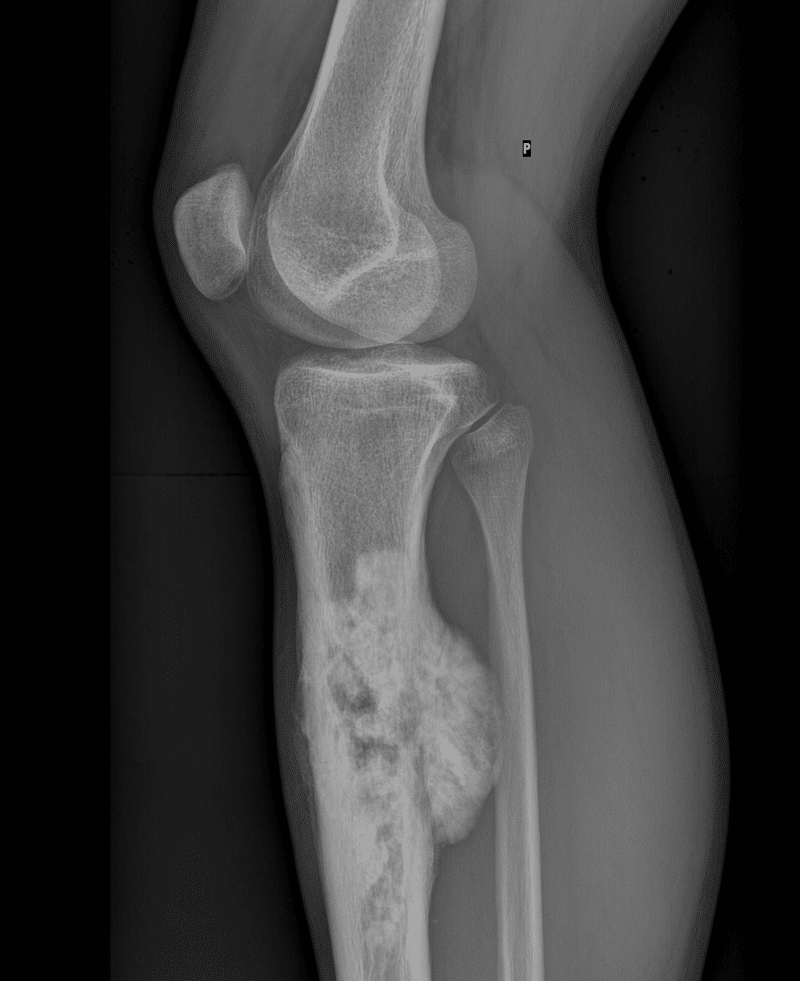

Osteosarcoma

This x-ray shows the aggressive nature of the infiltrative process of osteosarcoma.